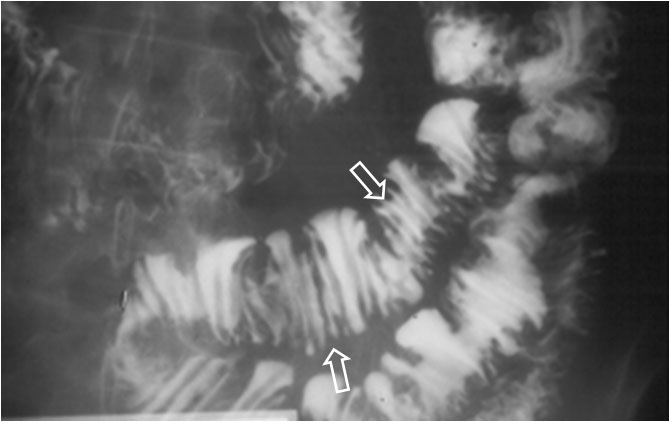

SIGNO DEL MOLDE

Recibe este nombre el aspecto de la luz del yeyuno en el esprúe avanzado o no tratado, en el estudio de tránsito intestinal baritado. Los pliegues mucosos aparecen borrados y el bario que llena la luz del intestino adopta la forma de un tubo relleno de cera endurecida. Habitualmente se asocia a segmentación marcada e hipersecreción (que no están presentes en esta imagen, que es una fotografía localizada en fosa iliaca izquierda de un tránsito intestinal).

Otro paciente con esprúe avanzado mostrando este signo. La apariencia de las asas intestinales en la radiografía se ha equiparado también al aspecto de la pasta de dientes.

En la literatura médica no es infrecuente encontrar este signo con su nombre original en francés: moulage o Signo del moulage.